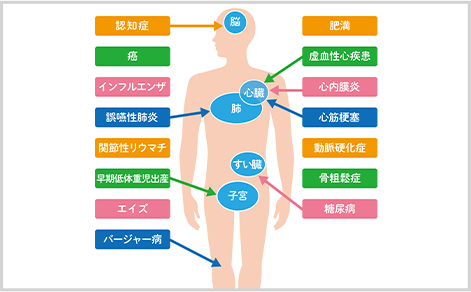

歯周病が全身に与える影響

歯周病は唾液や血液を介して体内に入り込むことで、全身疾患の原因にも繋がります。

糖尿病

歯周病の原因となる細菌が血糖値を下げるインスリンの働きを抑制してしまい、糖尿病のリスクが高まるだけでなく、悪化させる恐れがあります。また、高血糖の状態は唾液の分泌量を減らしてしまい、細菌が繁殖しやすくなるため歯周病になるリスクが高まります。

心疾患

重症化すると歯周病の炎症から血栓(血の固まり)ができやすくなるため、動脈硬化が引き起こされ、心筋梗塞や狭心症などの心疾患のリスクが高まります。

早産

細菌や炎症が胎盤を通じて胎児の成長や子宮の収縮などに影響を与え、早産や低体重児出産などを引き起こす恐れがあります。